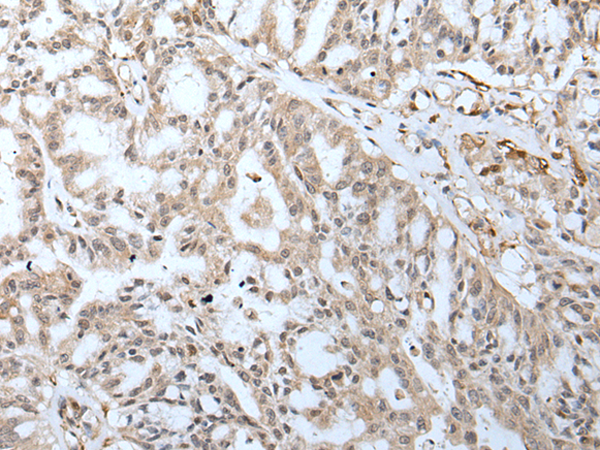

分类: 科研抗体货号: P12782别名: DEL5q14.3; C5DELq14.3应用: IHC反应种属: Human, Mouse